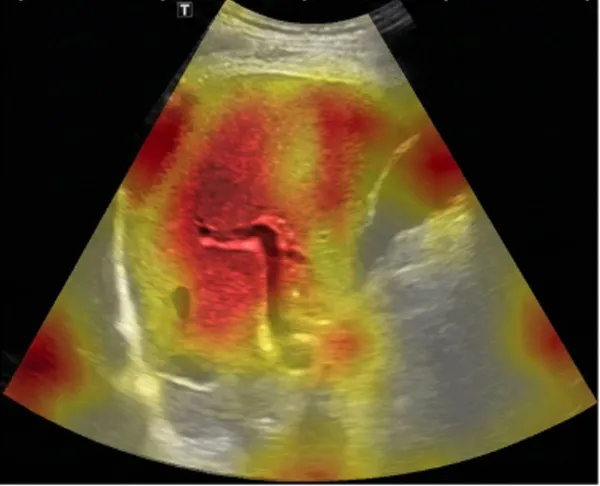

SmartLiva ทำงานเหมือน “อัปเกรด” จากภาพอัลตราซาวด์ขาวดำธรรมดาให้กลายเป็นผลวินิจฉัยที่อ่านง่ายและแม่นยำ โดยแพทย์จะอัปโหลดภาพผ่านเว็บได้ทั้งบนคอมพิวเตอร์หรือแท็บเล็ต จากนั้นระบบจะช่วยปรับภาพให้ชัดขึ้น คัดเฉพาะบริเวณเนื้อตับที่ต้องวิเคราะห์ และทำให้ภาพดูเข้าใจง่ายขึ้นด้วยการไฮไลต์เป็นสี (เช่น ตับเป็นสีแดง ไขมันเป็นสีเหลือง) เพื่อให้เห็นความผิดปกติได้ทันที

โดย AI จะทำการประเมิน 3 เรื่องพร้อมกัน คือ ประเมินระดับพังผืด/ความแข็งของตับ (F0–F4), ตรวจหาความผิดปกติของเนื้อเยื่ออย่างถุงน้ำหรือมะเร็งตับ และตรวจหาพยาธิใบไม้ตับ ซึ่งตัว AI จะทำการประมวล วิเคราะห์ และสรุปผลออกมาเป็นรายงานพร้อมภาพประกอบและคำอธิบายที่คนทั่วไปเข้าใจได้